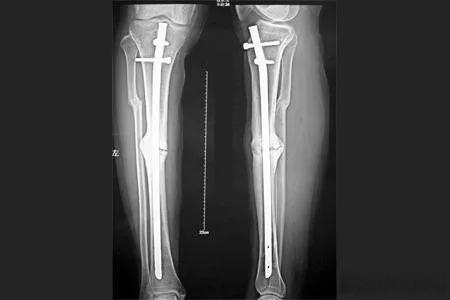

腓骨骨折是指发生在小腿腓骨的骨折,常见于青壮年和儿童。这种骨折通常由直接暴力(如重物撞击或车轮碾压)或间接暴力(如高处跌落、强烈扭转)引起。由于腓骨的前缘和前侧较表浅,骨折后容易穿破皮肤,形成开放性骨折。如果发生在中下段,还可能导致延迟愈合或不愈合。

值得注意的是,腓骨骨折的恢复时间因人而异。一般来说,轻度骨折可能需要6-8周,而更严重的骨折可能需要3-6个月。在这段时间里,患者需要定期复查,通常在出院后3个月、6个月、1年进行X线片检查,以了解骨折愈合情况。